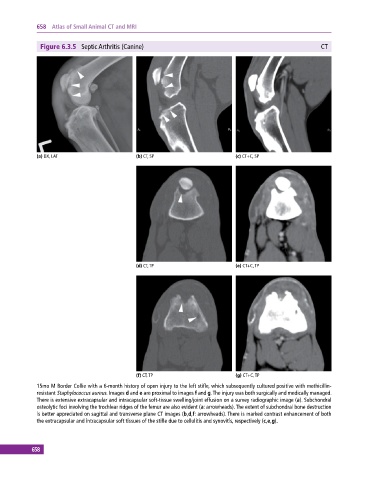

Figure 6.3.5 Septic Arthritis (Canine) CT

(a) DX, LAT (b) CT, SP (c) CT+C, SP

(d) CT, TP (e) CT+C, TP

(f) CT, TP (g) CT+C, TP

15mo M Border Collie with a 6‐month history of open injury to the left stifle, which subsequently cultured positive with methicillin‐

resistant Staphylococcus aureus. Images d and e are proximal to images f and g. The injury was both surgically and medically managed.

There is extensive extracapsular and intracapsular soft‐tissue swelling/joint effusion on a survey radiographic image (a). Subchondral

osteolytic foci involving the trochlear ridges of the femur are also evident (a: arrowheads). The extent of subchondral bone destruction

is better appreciated on sagittal and transverse plane CT images (b,d,f: arrowheads). There is marked contrast enhancement of both

the extracapsular and intracapsular soft tissues of the stifle due to cellulitis and synovitis, respectively (c,e,g).